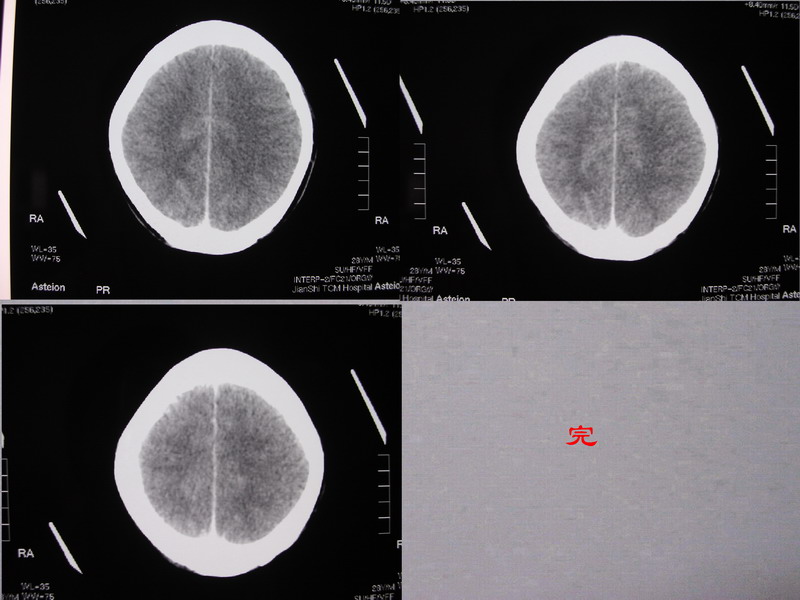

以下是引用余辉在2007-5-14 17:03:00的发言:[br]右侧脑室颞极后方可见高密度块状影,颞极呈杯口状推挤前移,右侧大脑脚及丘脑上部受推挤向对侧移位,右丘脑区结构紊乱,增强扫描病灶有不规则强化,以下部颞极后方为著。胼胝体压部及右枕叶视辐射区低密度改变,右基底节区低密度改变,双侧脑室不对称积水征象,意见:1颞极后方—右丘脑区占位性病变,如室管膜瘤等2脑血管疾病如moyamoya,局部脑血管畸形等3脑膜炎等后遗改变,建议mr及脑血管造影检查[br][br][本贴已被 余辉 于 2007-5-14 17:05:26 修改过]

以下是引用千里草在2007-5-14 15:54:00的发言:[br]考虑:1、双侧梗阻性脑积水;[br] 2、右侧基底节区缺血性脑血管疾病。